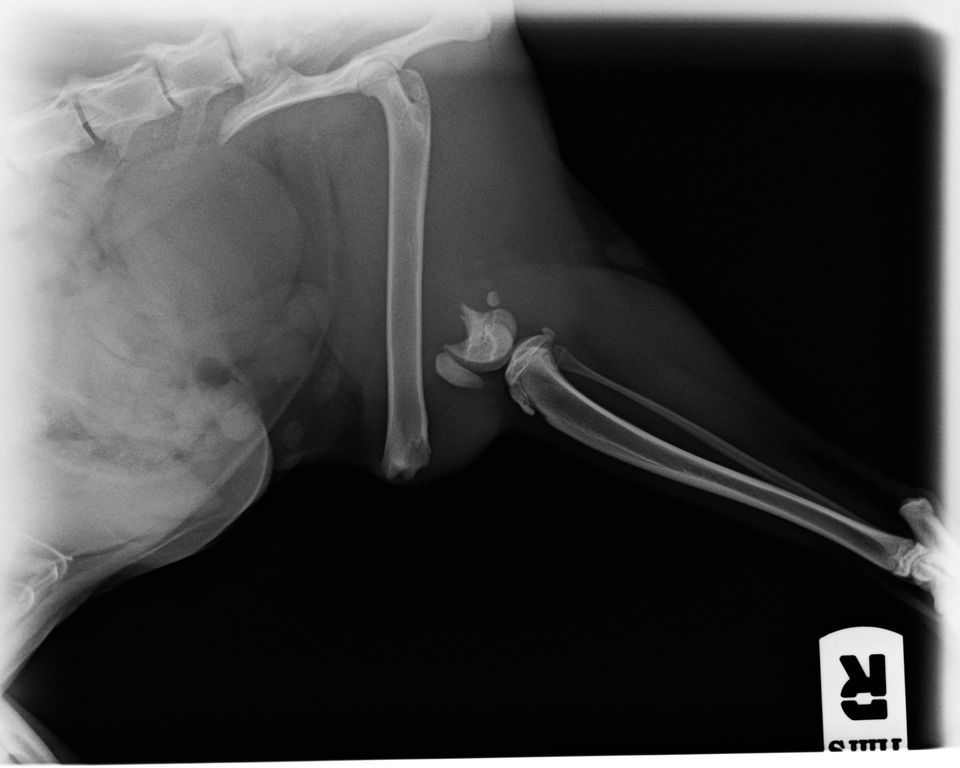

Hüfte: Luxationen (Operation nach Slocum, Kapselplastik, Toggle Pin - Methode), Kapselraffung, Femurkopfhalsresektionen

Kreuzbandriss: Die chirurgische Therapie des vorderen Kreuzbandrisses erfolgt bei uns entweder mit der sogenannten extrakapsulären Fadenzügeltechnik oder durch eine TPLO (Tibia Plateau Leveling Osteotomie, die bei großen Hunden die besten Langzeitergebnisse liefert)

Patellaluxation: Korrektur mittels Sulcusvertiefung, Transposition der Tuberositas tibiae, Kapselraffung